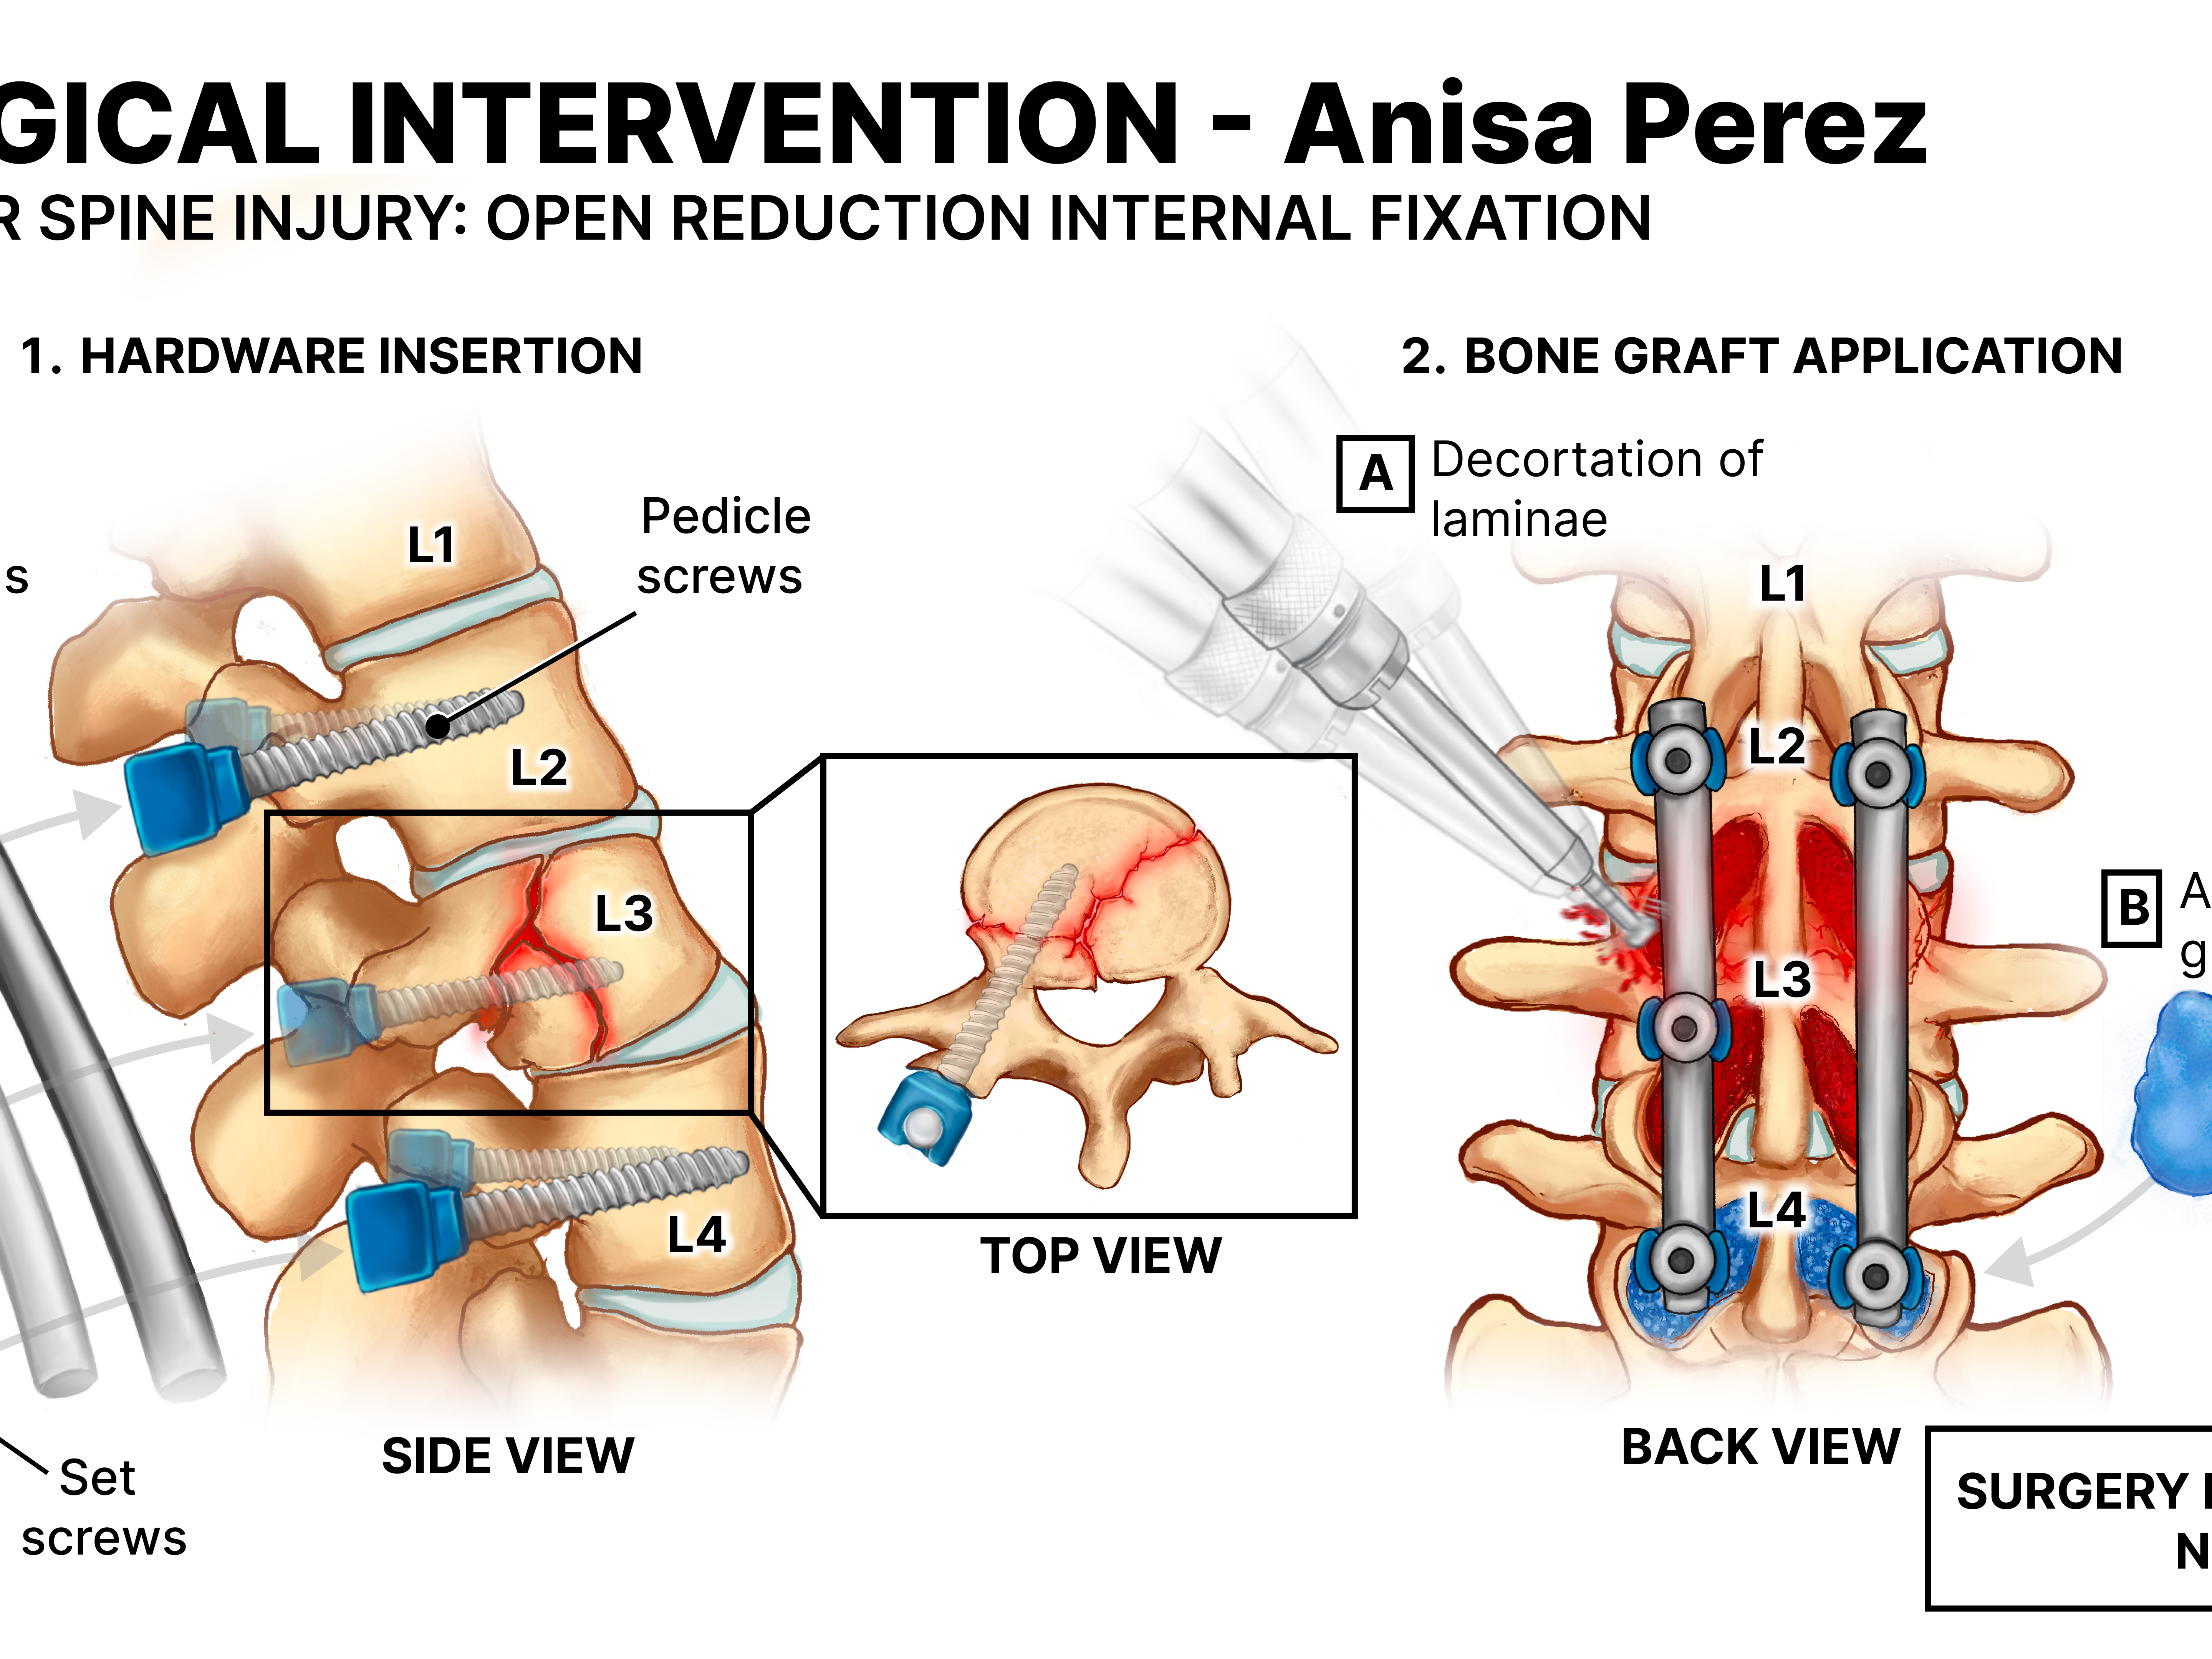

Medical Legal Exhibit: Lumbar Spine Injury

2025

Demonstrative Evidence for the Courtroom | Procreate, Illustrator | Client: Stephen Mader